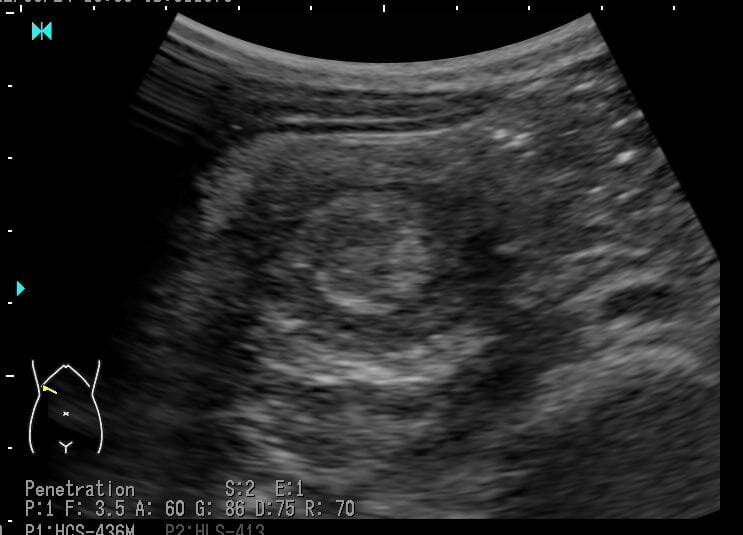

一照超音波,就看到一個像「甜甜圈」的病灶。陳敬倫醫生說,腸套疊是相當危險的疾病,屬兒科常見的急症之一,其原因不明,但可能與腺病毒感染、腸黏膜淋巴結腫大有關。此病好發於1歲前(3個月至6歲),且大部分病徵是「大腸套小腸」的形式。

Photo from 臭寶爸 - 兒科陳敬倫醫師 facebook

陳敬倫表示,雖然腸套疊的超音波檢查準確度高達100%,但有時腸套疊出現的症狀和腸胃炎非常像,因此若家中孩子腸胃炎治療沒有明顯改善,或有吐膽汁(綠色)、劇烈腹痛、血便等危險徵兆,一定要進一步做檢查,早點發現才能盡早治療。